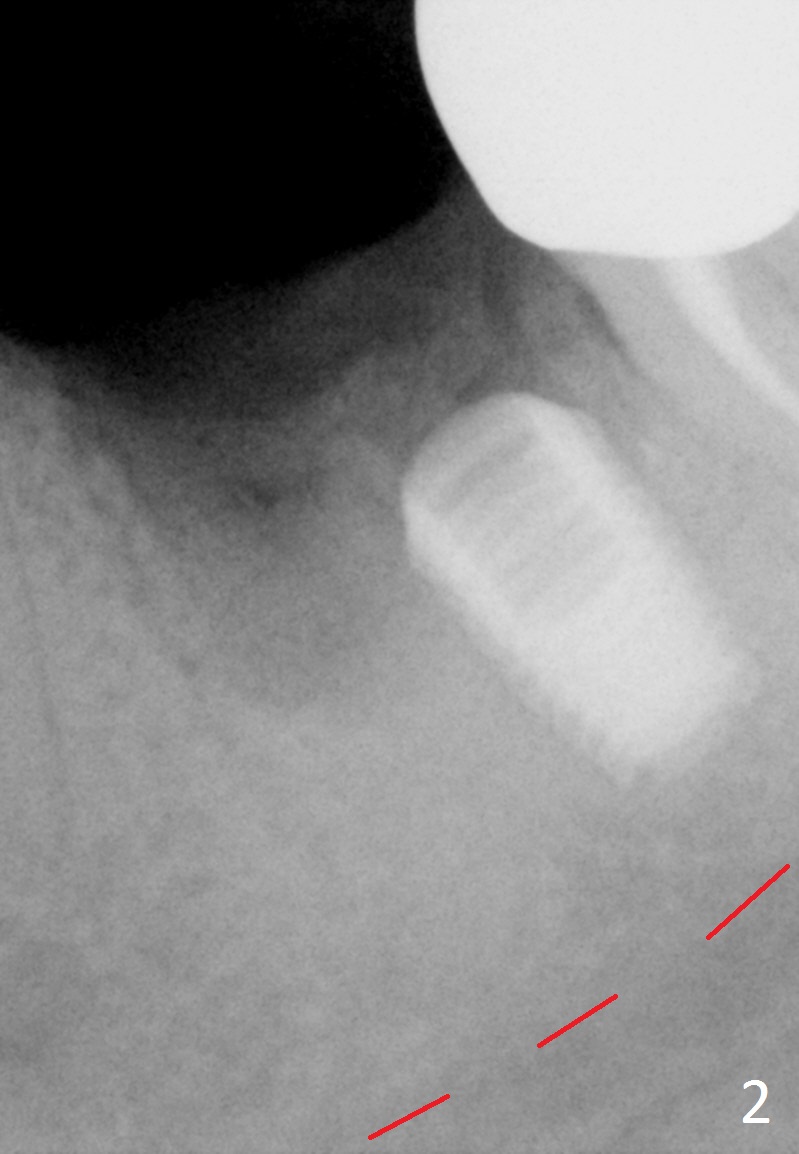

Etiology of Periimplantitis A 42-year-old woman presented to clinic 11 years ago with history of extraction of the tooth #19 two months earlier (Fig.1). Two months later, a 5x8 mm Bicon implant was placed (Fig.2). Integrated Abutment Crown was delivered 2 years later (Fig.3) with persistent radiolucency in the mesial socket. The tooth #18 was extracted with socket preservation 7 years ago. Recently she returned with chief complaint of chewing pain in the lower left for a while. The buccal gingiva of #19 is erythematous, edematous and tender (Fig.4). There are healing abutment at #29 and implant crown at #30. Periimplantitis at #19 is most likely due to buccodistal placement. When it is removed (Clindamycin), a smaller IBS or SM implant will be placed immediately and mesiolingually (Fig.3). For better wound protection with periodontal dressing or provisional, an implant will be placed at #18 at the same appointment. Draw blood for PRF if the vein is large enough. Surgical stents have been in cold sterilant. Return to Lower Molar Immediate Implant, Prevent Molar Periimplantitis (Protocols, Table), Course 1 2 Fig.1 Remedy Xin Wei, DDS, PhD, MS 1st edition 06/16/2017, last revision 06/26/2020 |